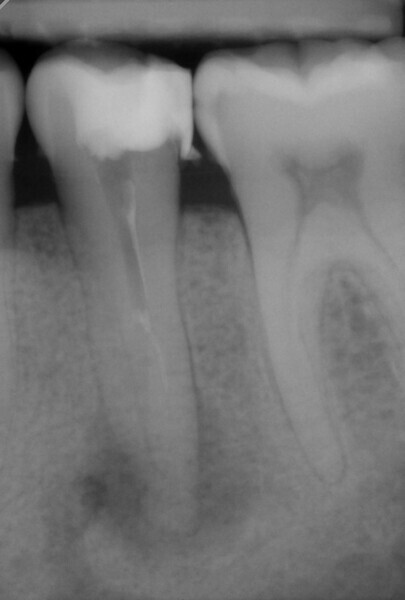

Obturation and final restoration with a fibre post were performed at the second appointment. The radiograph confirmed that I had been able to treat both root canals along the entire length of the tooth (approximately 23 mm) with minimal loss of tooth structure and in the most conservative manner possible (Fig. 6).

The follow-up appointments observed complete healing of the treated tooth (Fig. 7). Together with the patient, we decided that a crown was not necessary for the moment.